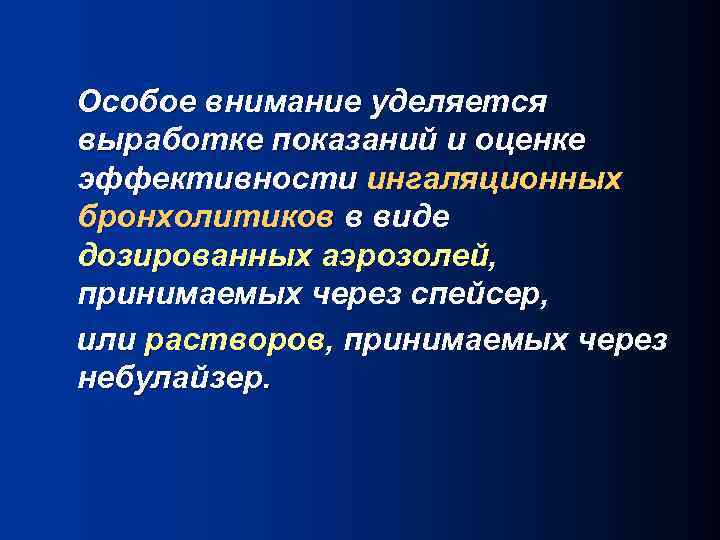

Особое внимание уделяется выработке показаний и оценке эффективности ингаляционных бронхолитиков в виде дозированных аэрозолей, принимаемых через спейсер, или растворов, принимаемых через небулайзер.